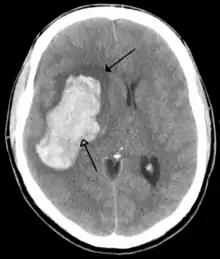

![]() | |

| CT scan of the brain showing a prior right-sided ischemic stroke from blockage of an artery. Changes on a CT may not be visible early on.[1] | |

The main risk factor for stroke is high blood pressure.[6] Other risk factors include tobacco smoking, obesity, high blood cholesterol, diabetes mellitus, a previous TIA, end-stage kidney disease, and atrial fibrillation.[2][6][7] An ischemic stroke is typically caused by blockage of a blood vessel, though there are also less common causes.[12][13][14] A hemorrhagic stroke is caused by either bleeding directly into the brain or into the space between the brain's membranes.[12][15] Bleeding may occur due to a ruptured brain aneurysm.[12] Diagnosis is typically based on a physical exam and supported by medical imaging such as a CT scan or MRI scan.[8] A CT scan can rule out bleeding, but may not necessarily rule out ischemia, which early on typically does not show up on a CT scan.[9] Other tests such as an electrocardiogram (ECG) and blood tests are done to determine risk factors and rule out other possible causes.[8] Low blood sugar may cause similar symptoms.[8]

Stroke is diagnosed through several techniques: a neurological examination (such as the NIHSS), CT scans (most often without contrast enhancements) or MRI scans, Doppler ultrasound, and arteriography. The diagnosis of stroke itself is clinical, with assistance from the imaging techniques. Imaging techniques also assist in determining the subtypes and cause of stroke. There is yet no commonly used blood test for the stroke diagnosis itself, though blood tests may be of help in finding out the likely cause of stroke.[62]

CT scans may not detect an ischemic stroke, especially if it is small, of recent onset, or in the brainstem or cerebellum areas. A CT scan is more to rule out certain stroke mimics and detect bleeding.[9]